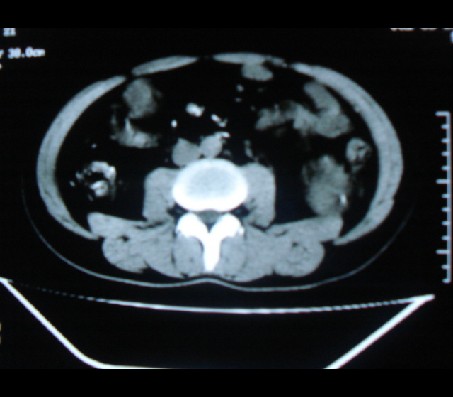

标题: CT20935:左肾占位,请会诊!

男性,35岁,ct号26189,左侧腰痛并血尿一天入院。

左肾癌侵犯肾盂可能性大,建议增强

左肾癌侵犯肾盂可能性大。